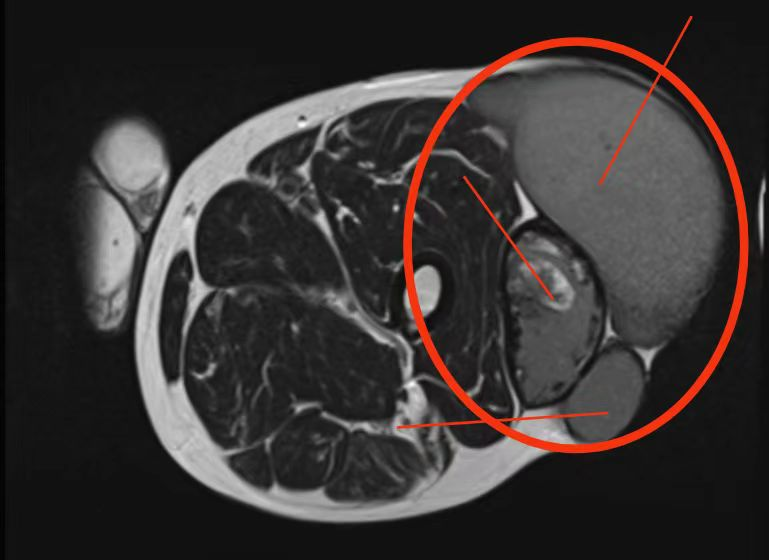

入院时莫伯左大腿肿物较大,约28*18cm,局部轻压痛,不排除恶变可能,需要尽快切出肿物检查。MRI检查提示左大腿肿物由几个小肿瘤聚在一起,相互粘连。考虑到患者年龄大,肿物也异常大,手术难度极大。面对患者目前状况,陆明博士带领骨科团队反复讨论及认真研究,最终为莫伯制定严密的手术方案。

MRI显示腿部肿瘤

在陆明博士的带领下,骨科团队对患者行肿瘤切除手术,手术历时不到1小时,彻底将患者腿部的巨大肿瘤切除。术后病理检测提示为良性肿瘤,但不排除恶变可能。尽早切除肿瘤可以避免错失治疗时间和肿物恶变。患者伤口愈合良好,术后3天可自行下地活动,1周后好转出院。